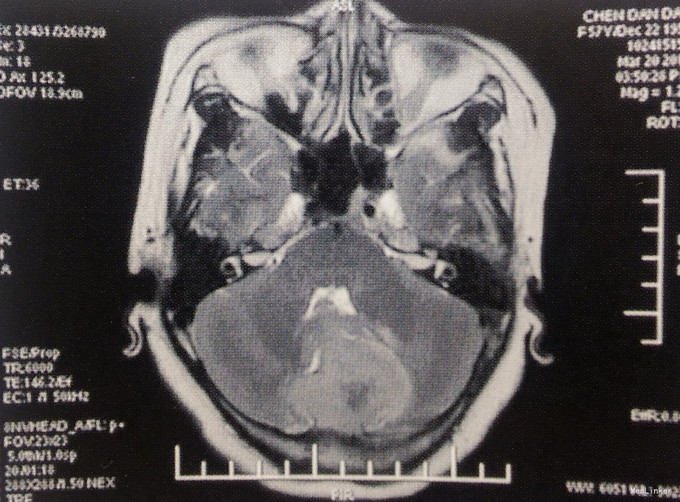

体格检查:神经系统未见阳性体征。 术前影像学检查 头颅MRI检查:小脑幕下两侧小脑半球脑外占位性病变,左侧病变为著,边界清楚,第四脑室受压变窄,幕上脑室轻度积水,增强扫描病变明显均匀强化,考虑脑膜瘤可能性大。